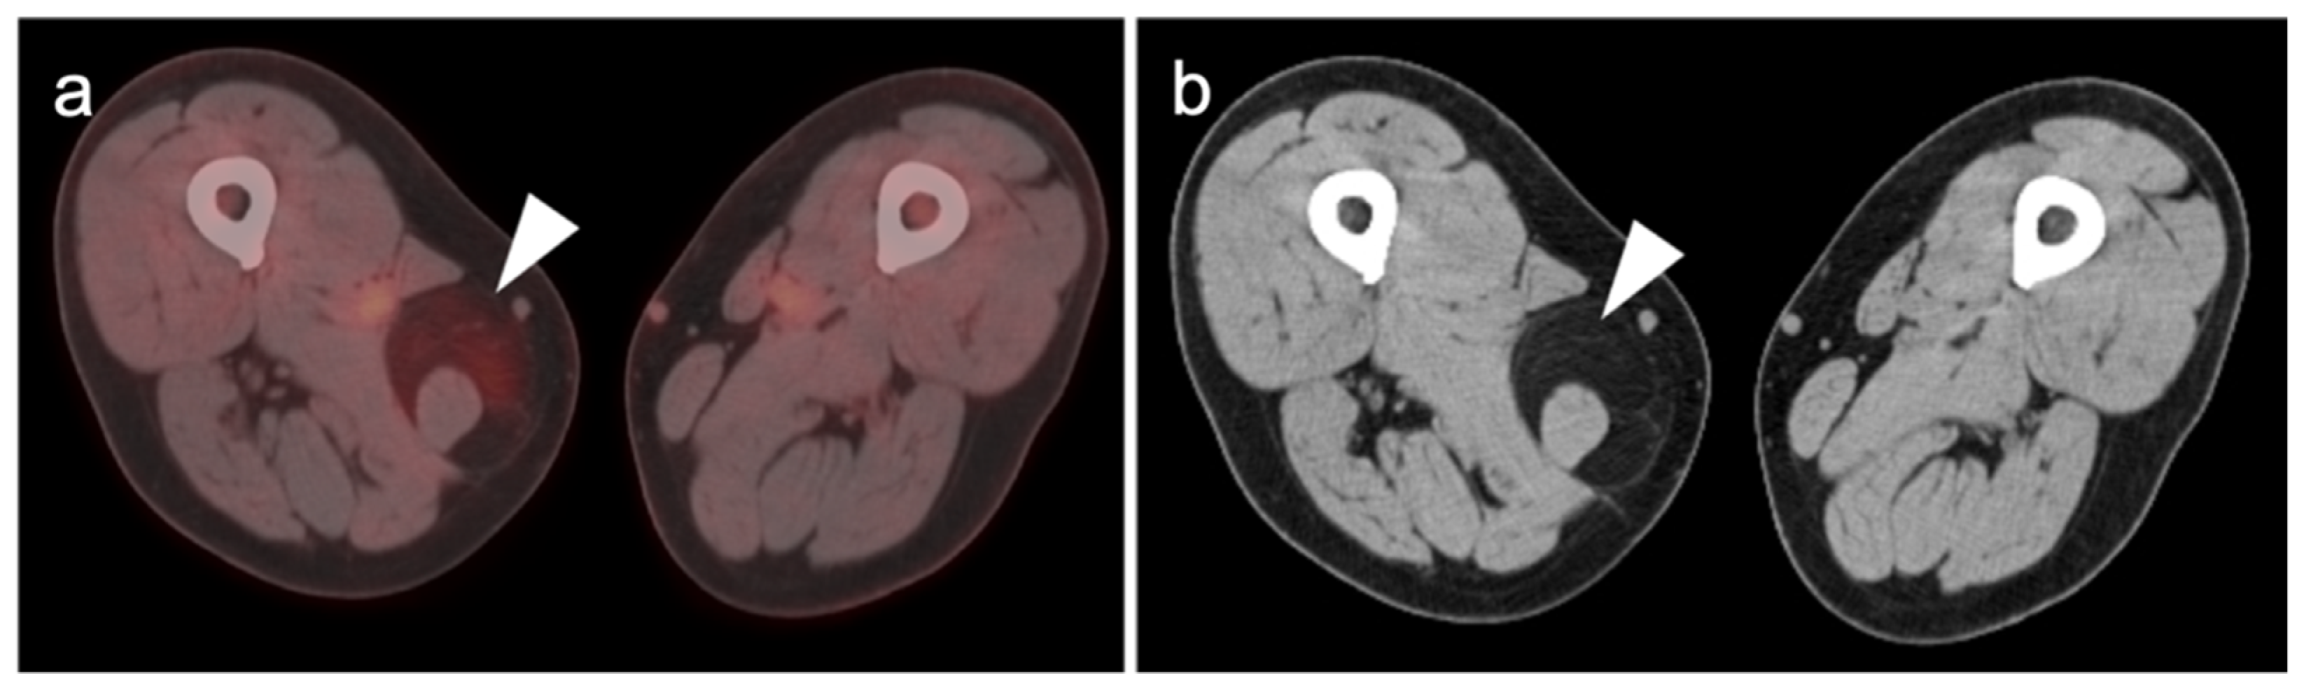

- Uslu, L.; Asa, S.; Sager, S.; Halaç, M. Multiple cardiac masses and distant metastatic foci in a patient with high grade pleomorphic sarcoma of the heart revealed by follow-up FDG PET/CT. Nukl.-Nucl. 2014, 53, N8–N9. [Google Scholar] [CrossRef]